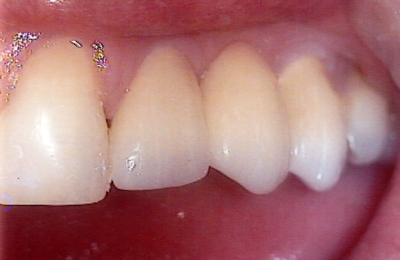

See the results

Drag the sliders below to see some of the amazing results achieved by other Lumino patients and our experienced team of dentists.

Bridge 3 Before Bridge 3 After